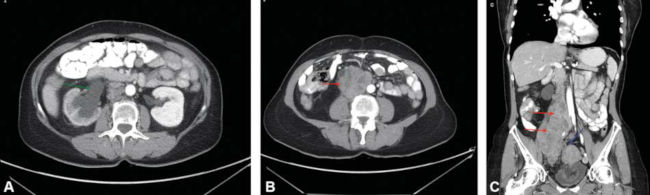

Se completó con tomografía computada (TC) tras administración de contraste intravenoso y oral en fase venosa, identificándose una gran masa retroperitoneal derecha, de 19 × 9,3 × 8,3 cm aproximadamente. Engloba al uréter y vena cava inferior hasta su bifurcación, a la vena iliaca común, externa e interna derechas, en contacto con la aorta abdominal (►Fig. 2). Tiene contornos polilobulados y atenuación heterogénea con áreas hipodensas centrales, sin grasa macroscópica ni calcificaciones y moderado realce tras la administración de contraste intravenoso. Está en íntimo contacto con el músculo psoas, los cuerpos vertebrales derechos (L3-S1) y la cúpula uterina, en el que se observan leiomiomas, sin signos de infiltración de los mismos ni metástasis.